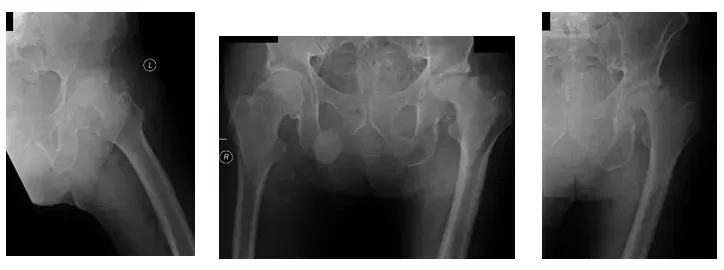

La paciente es una mujer de 55 años que acudió con fuertes dolores. La paciente explicó que hace tres años tuvo una fractura intertrocantérica de la cadera izquierda y una fijación interna de reducción abierta (ORIF) realizada por una institución externa. Afirmó que...